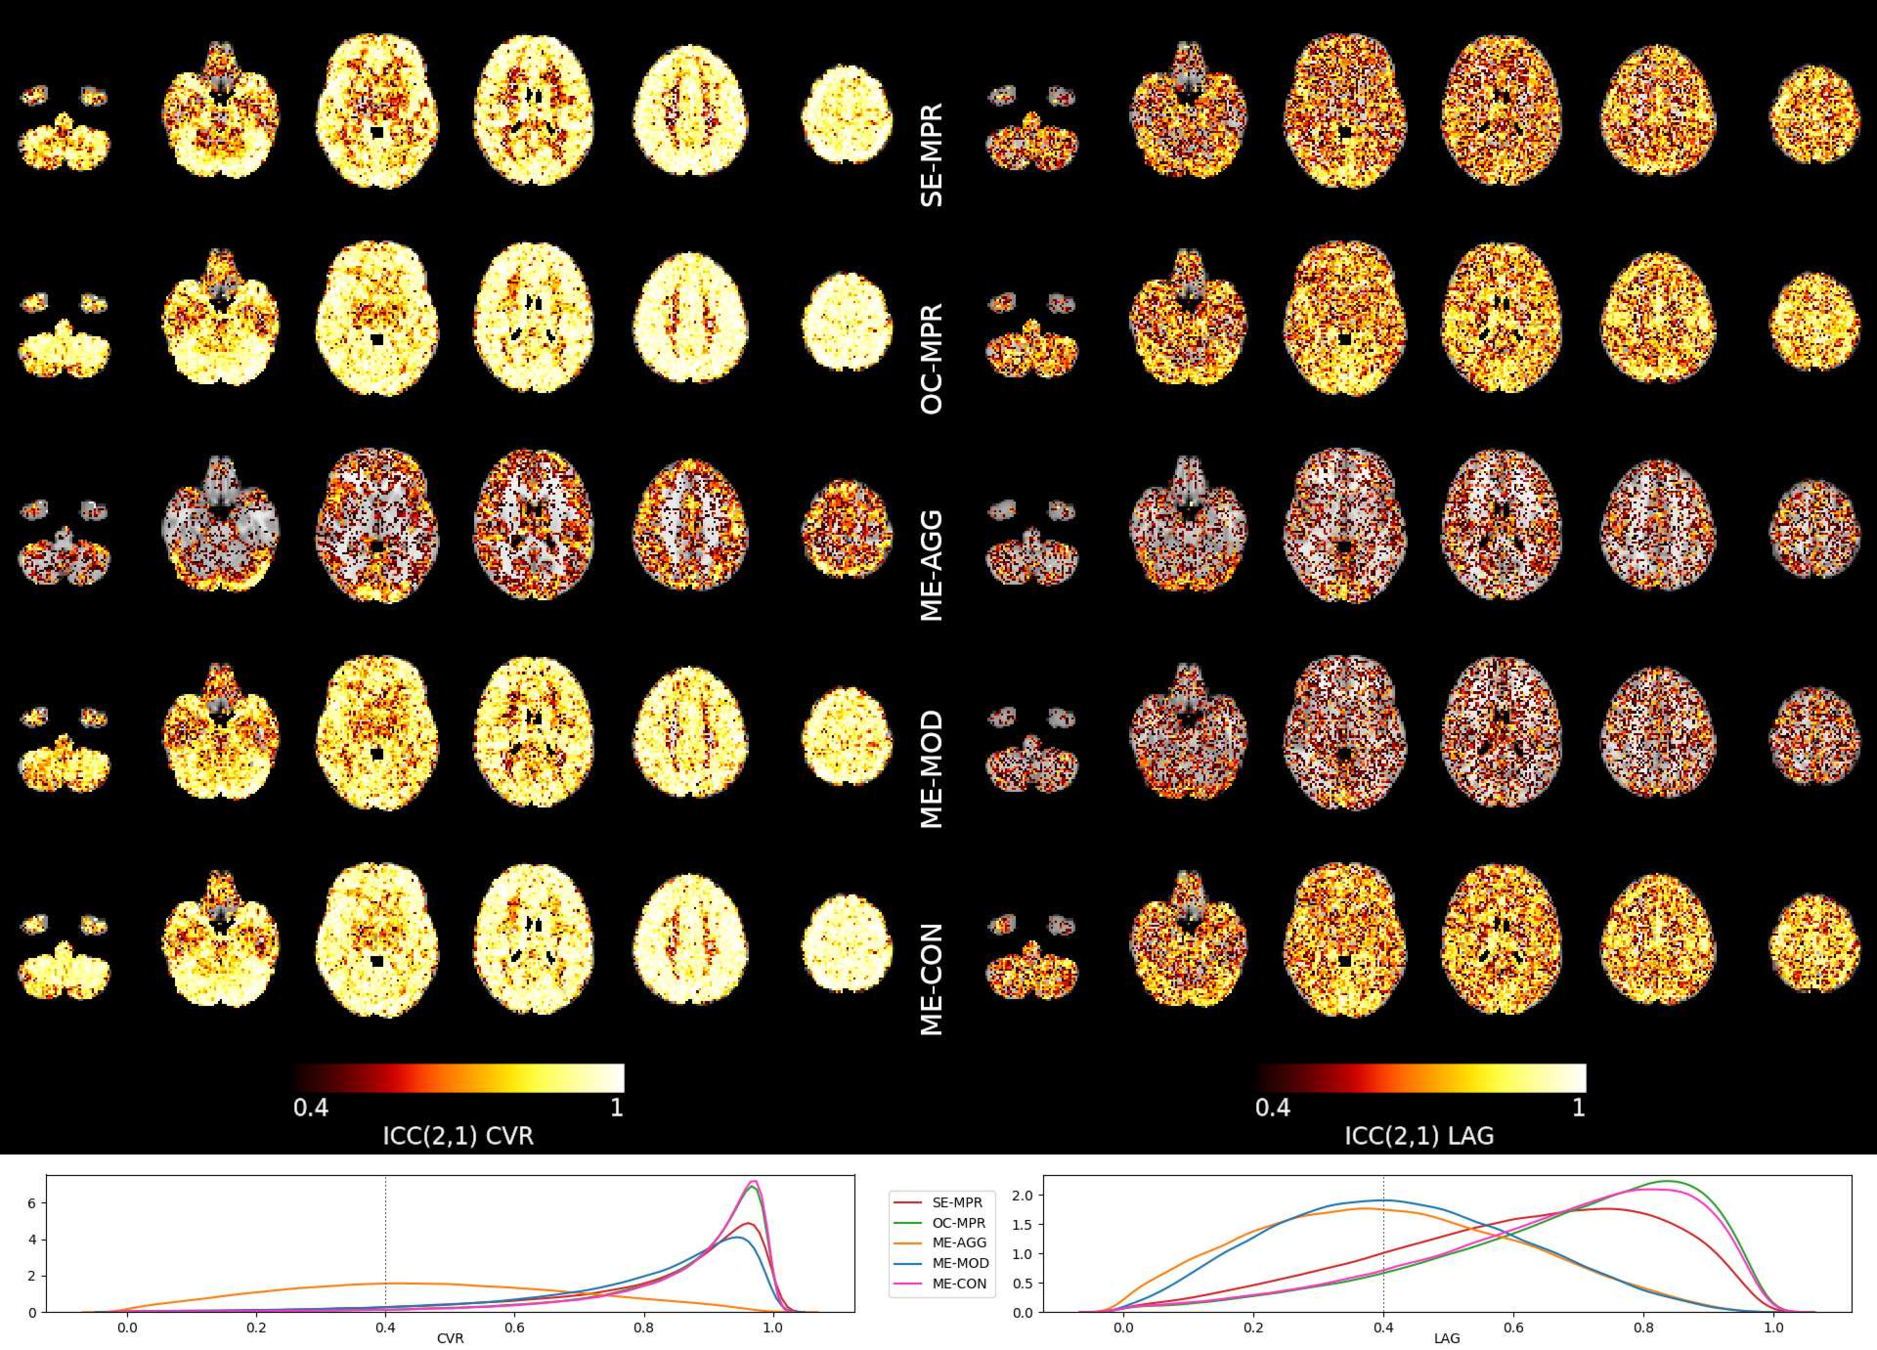

Methods: ME-ICA based denoise

- the resulting CVR and lag maps spatially [LME]: $$X\sim model+(1|subject)+(1|session)$$

- the resulting CVR and lag maps' reliability [ICC]: $$X \sim (1|subject)+(1|session)$$

Reliability [ICC (2,1)]

Moia et al. 2021 (NeuroImage)

OC-MPR vs ME-CON

ME-CON should be better than OC-MPR in temporal-dependent application

Conclusion

In data characterised by global responses and high motion collinearity, such as CVR, a conservative ICA-based approach best removes motion-related effects, while obtaining reliable responses, but a simple optimal combination of ME data provides similar estimations

However, further examinations are required to translate these observations to paradigms with lower collinear motion and more focal responses (e.g. functional task), or in which there is no task information available (e.g. rest)

An ICA-based conservative denoising improves BH-induced CVR mapping, but a simpler optimal combination of ME data could be already sufficient.